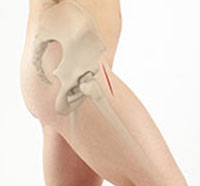

A gluteus medius tear is a condition characterized by severe strain on the gluteus medius muscle that results in partial or complete rupture of the muscle.